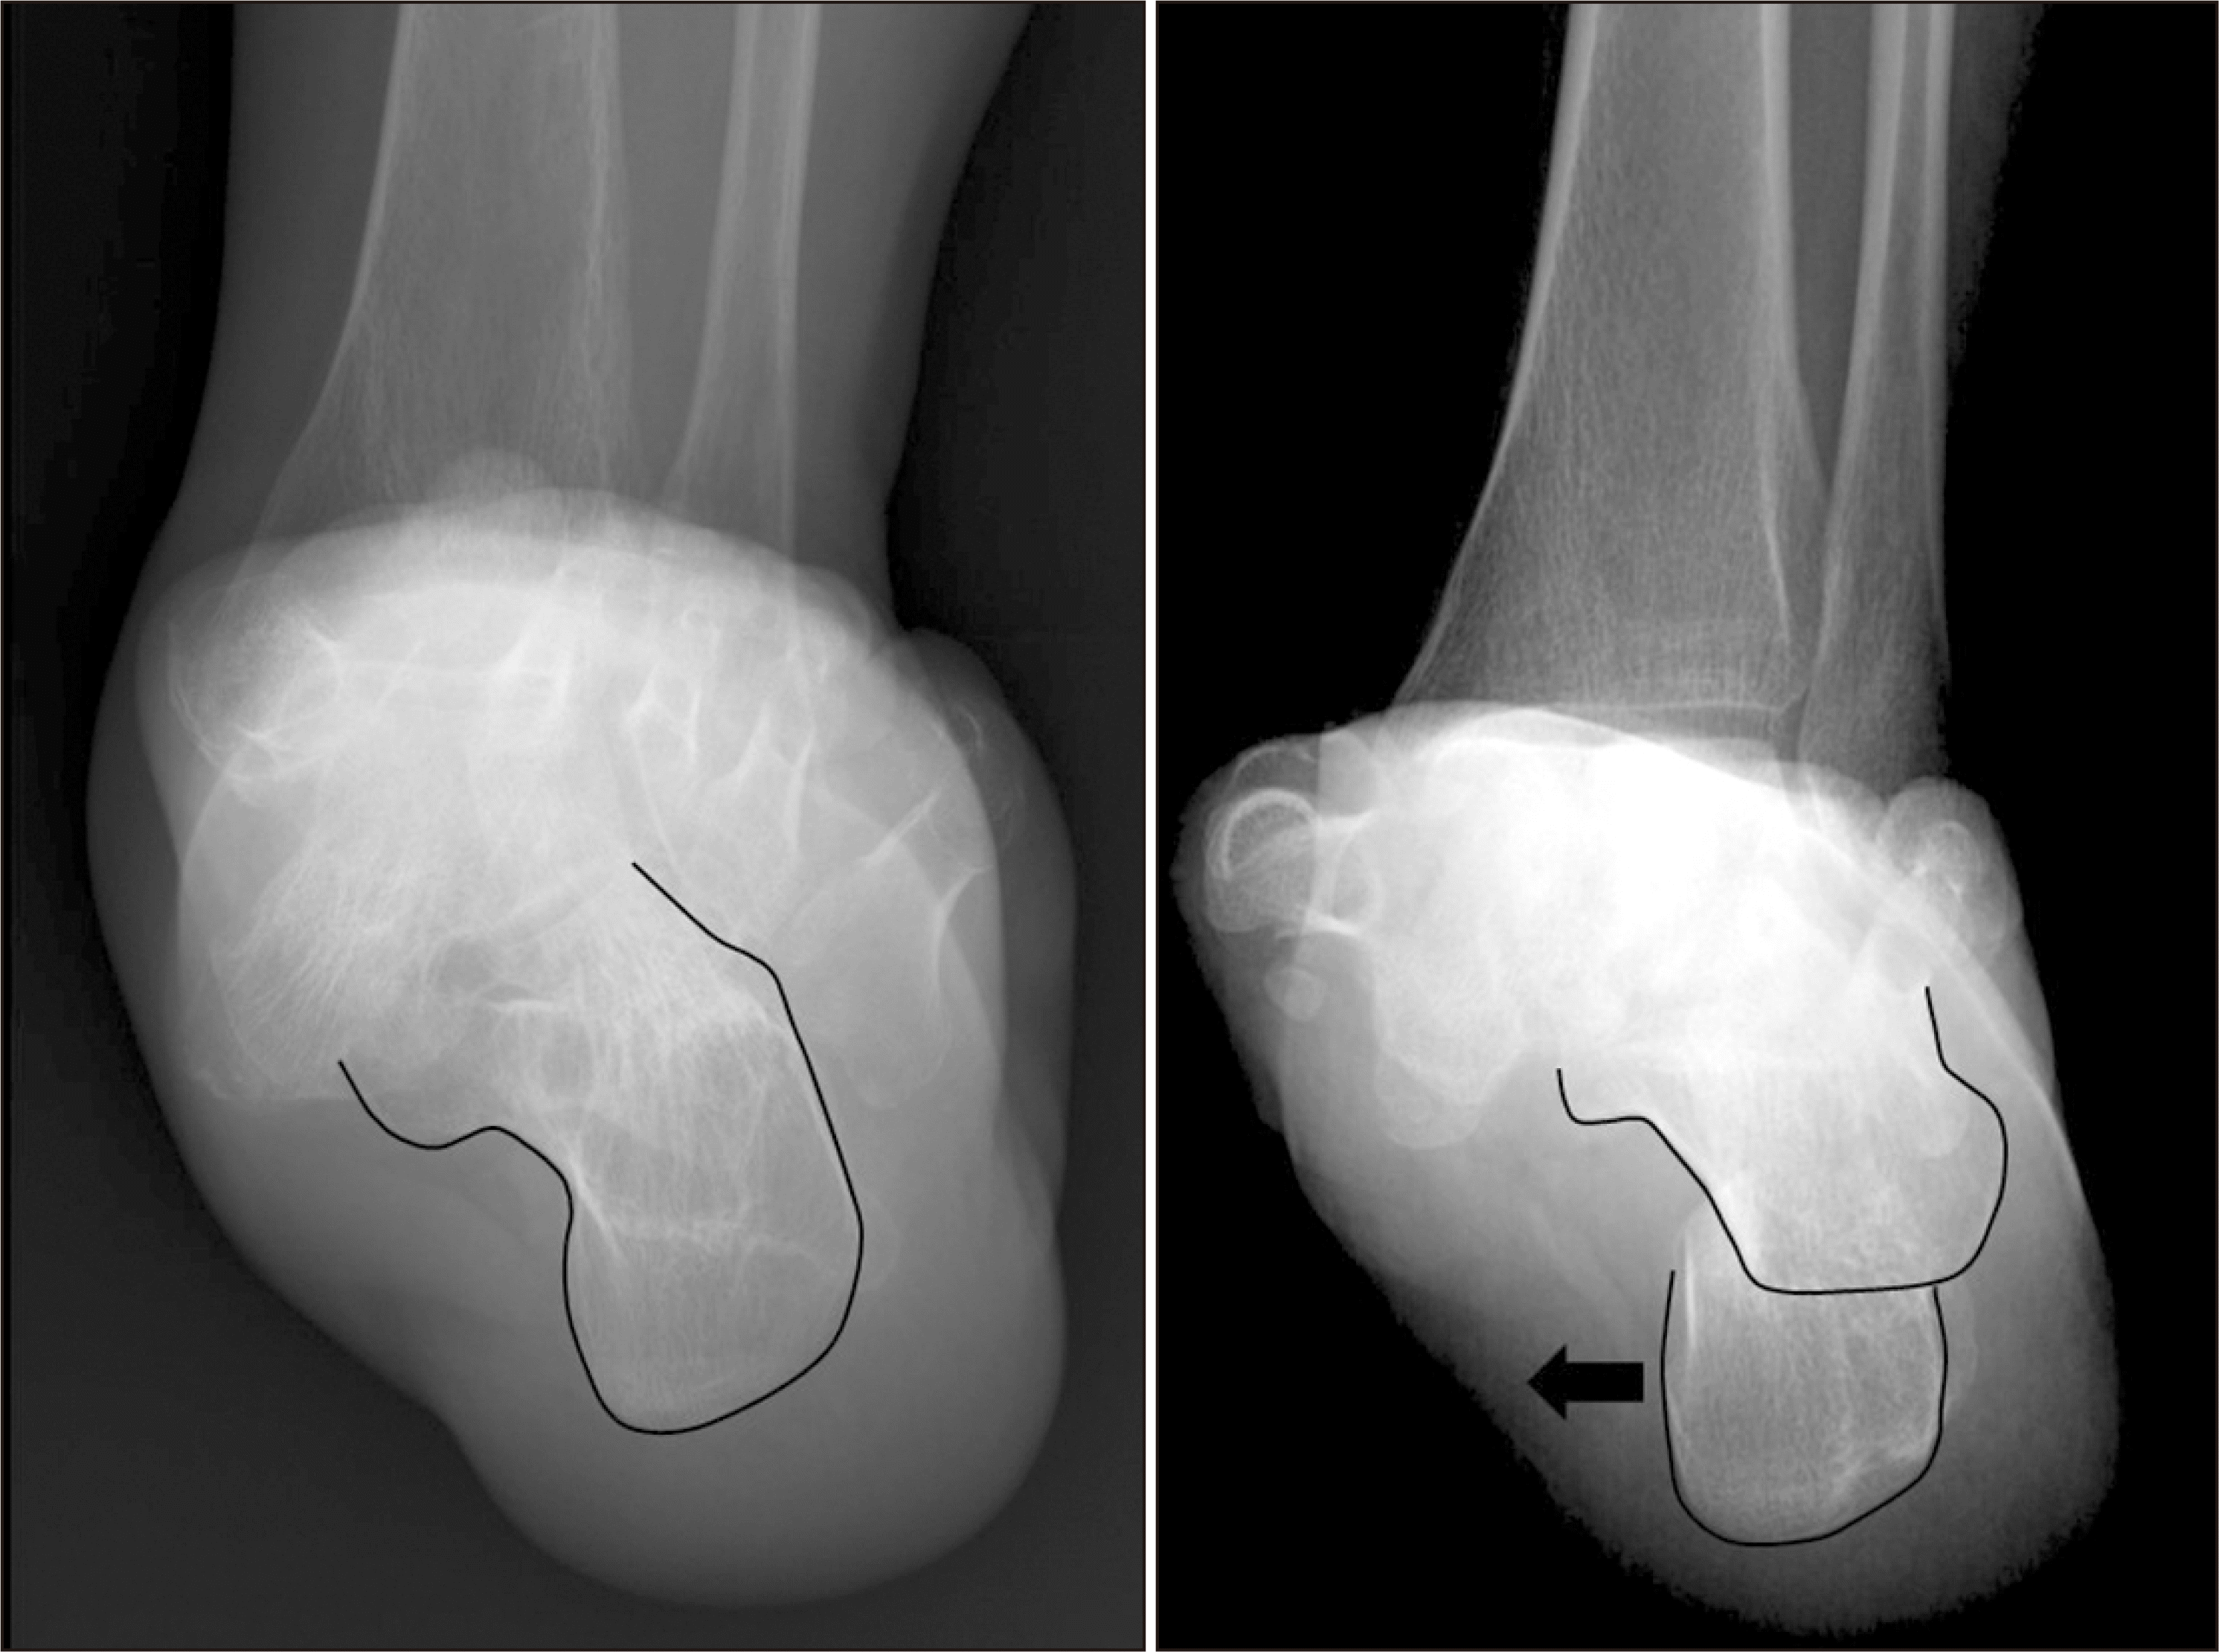

체중부하 방사선 촬영은 편평족의 진단에 있어 가장 표준이 되는 검사로, 체중부하 족부 전후면, 족부 측면, 족관절의 전후면 혹은 모티스 영상(mortise view) 및 후족부 정렬 촬영(hindfoot alignment view)8) 등이 진단을 위해 권고된다.9) 족부 전후면 사진에서는 전족부 혹은 중족부의 외전 정도를 평가할 수 있으며 거주상 관절 피복각(talonavicular coverage angle), 거주상 관절 이탈률(talonavicular uncoverage percent) 등 이를 반영하는 매우 다양한 지표를 측정할 수 있다(Fig. 1). 족부 측면 사진에서는 내측 세로궁의 소실 정도를 평가할 수 있는데, 흔히 쓰이는 지표로는 Meary angle이라 불리는 외측 거골-제 1중족골 각도를 측정할 수 있다(Fig. 2). 또한 족부의 내측주(medial column) 관절들의 족저부 벌어짐(plantar gapping) 정도를 확인하여 내측주 불안정성 정도를 평가할 수 있으며 족근동에서 거골과 종골의 직접적인 충돌 혹은 족근동 주변 골의 경화소견이나 낭종성 병변 등을 통해 족근동 충돌을 간접적으로 확인할 수 있다(Fig. 3). 족관절의 전후방 혹은 모티스 사진에서는 거골의 외반경사(valgus talar tilt)의 유무를 통해 족관절의 불안정성을 평가할 수 있으며 변형이 많이 진행한 경우 비골하 충돌 또한 확인할 수 있다(Fig. 4). 마지막으로, 후족부 정렬 촬영을 통해서는 후족부 외반 변형의 정도를 평가할 수 있는데, 주로 후족부 정렬각(hindfoot alignment angle) 혹은 후족부 모멘트암(hindfoot moment arm)을 측정한다(Fig. 5).10)

새로운 분류체계는 변형의 종류와 위치에 따라 A~E로 나누고, 각 변형의 유연성 유무에 따라 1기 유연성 변형과 2기 강직성 변형으로 분류하였다(Table 2).6) 이러한 변형은 진찰 소견과 체중부하 단순 방사선 촬영을 통해 평가하도록 하였고, 체중부하 전산화 단층촬영의 경우 아직 전세계적으로 사용되고 있지는 않기 때문에 판단기준에서 제외되었다. A형 변형은 후족부 외반 변형으로 후족부가 신체의 정중선으로부터 외측으로 전위된 변형을 뜻한다. 임상적으로 진찰 시 후족부 외반이 관찰되거나, 후족부 정렬 영상에서 후족부 정렬각 혹은 후족부 모멘트암의 증가 등으로 판단할 수 있다(Fig. 5). B형 변형은 전족부 혹은 중족부의 외전 변형으로 전족부나 중족부가 후족부를 기준으로 외측으로 전위된 변형이다. 체중부하 족부 전후면 사진상 거골두에 대한 주상골의 피복(coverage) 정도가 감소하고, 거주상 관절 피복각이 증가한다(Fig. 1). 또한 이 변형에 의해 족근동 충돌이 발생할 수 있으며, 족근동 주변의 압통 및 통증이 발생할 수 있다. 체중부하 족부 측면사진상 족근동에서 거골과 종골의 직접적인 충돌 소견이 보이거나, 족근동 주변의 거골과 종골의 골경화 혹은 골낭종 등을 통해 간접적으로 확인할 수 있다(Fig. 3). C형 변형은 전족부의 내반 변형 혹은 내측주 불안정성으로 임상적으로 후족부를 중립 위치에 고정한 뒤 관찰하였을 때 전족부가 내반을 보이는 변형이다(Fig. 8). 일부에서는 이를 회외 변형으로 불러야 한다는 의견도 있으나 현재 혼용해서 쓰이고 있다.11,20) 내측주 불안정성은 체중부하 족부 측면사진상 거주상 관절, 주상설상 관절(naviculocuneiform joint) 및 족근중족 관절(tarsometatarsal joint)이 배측 불안정증을 보이는 것으로, 영상검사상 족저부 벌어짐 유무 등을 통해 내측주 불안정성의 유무 및 위치를 확인할 수 있다(Fig. 3). D형 변형은 거근관절의 탈구 혹은 아탈구 변형으로 거골이 종골을 기준으로 내회전, 족저굴곡되면서 종골은 거골을 기준으로 외회전, 외반, 외측 전위가 발생하면서 거골하 관절의 아탈구가 발생하고, 심한 경우 비골하 충돌을 일으키게 된다(Fig. 4). E형 변형은 발목관절의 외반 변형이 발생한 경우이며, 족관절의 전후방 혹은 모티스 사진에서 거골의 외반경사로 확인할 수 있다(Fig. 4). 이 분류의 적용은 한 환자에 대해 A 부터 E까지의 변형 유무를 확인하고, 각각의 변형이 유연성 변형인지, 강직성 변형인지에 따라 1기와 2기를 나누는 방식으로 적용한다.

Figure 3

Weight bearing foot lateral radiograph showing plantar gapping of naviculocuneiform joint (*) and tarsometatarsal joint (**). Sinus tarsi impingement (black arrow) and bony sclerosis around sinus tarsi (white arrow).